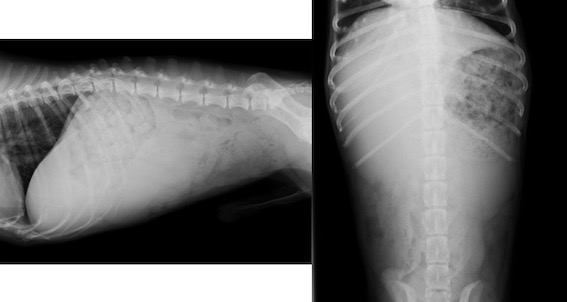

レントゲン検査画像です。

腹腔内に巨大なしこり(直径約8cm)が認められ、脾臓腫瘤であることが分かりました。